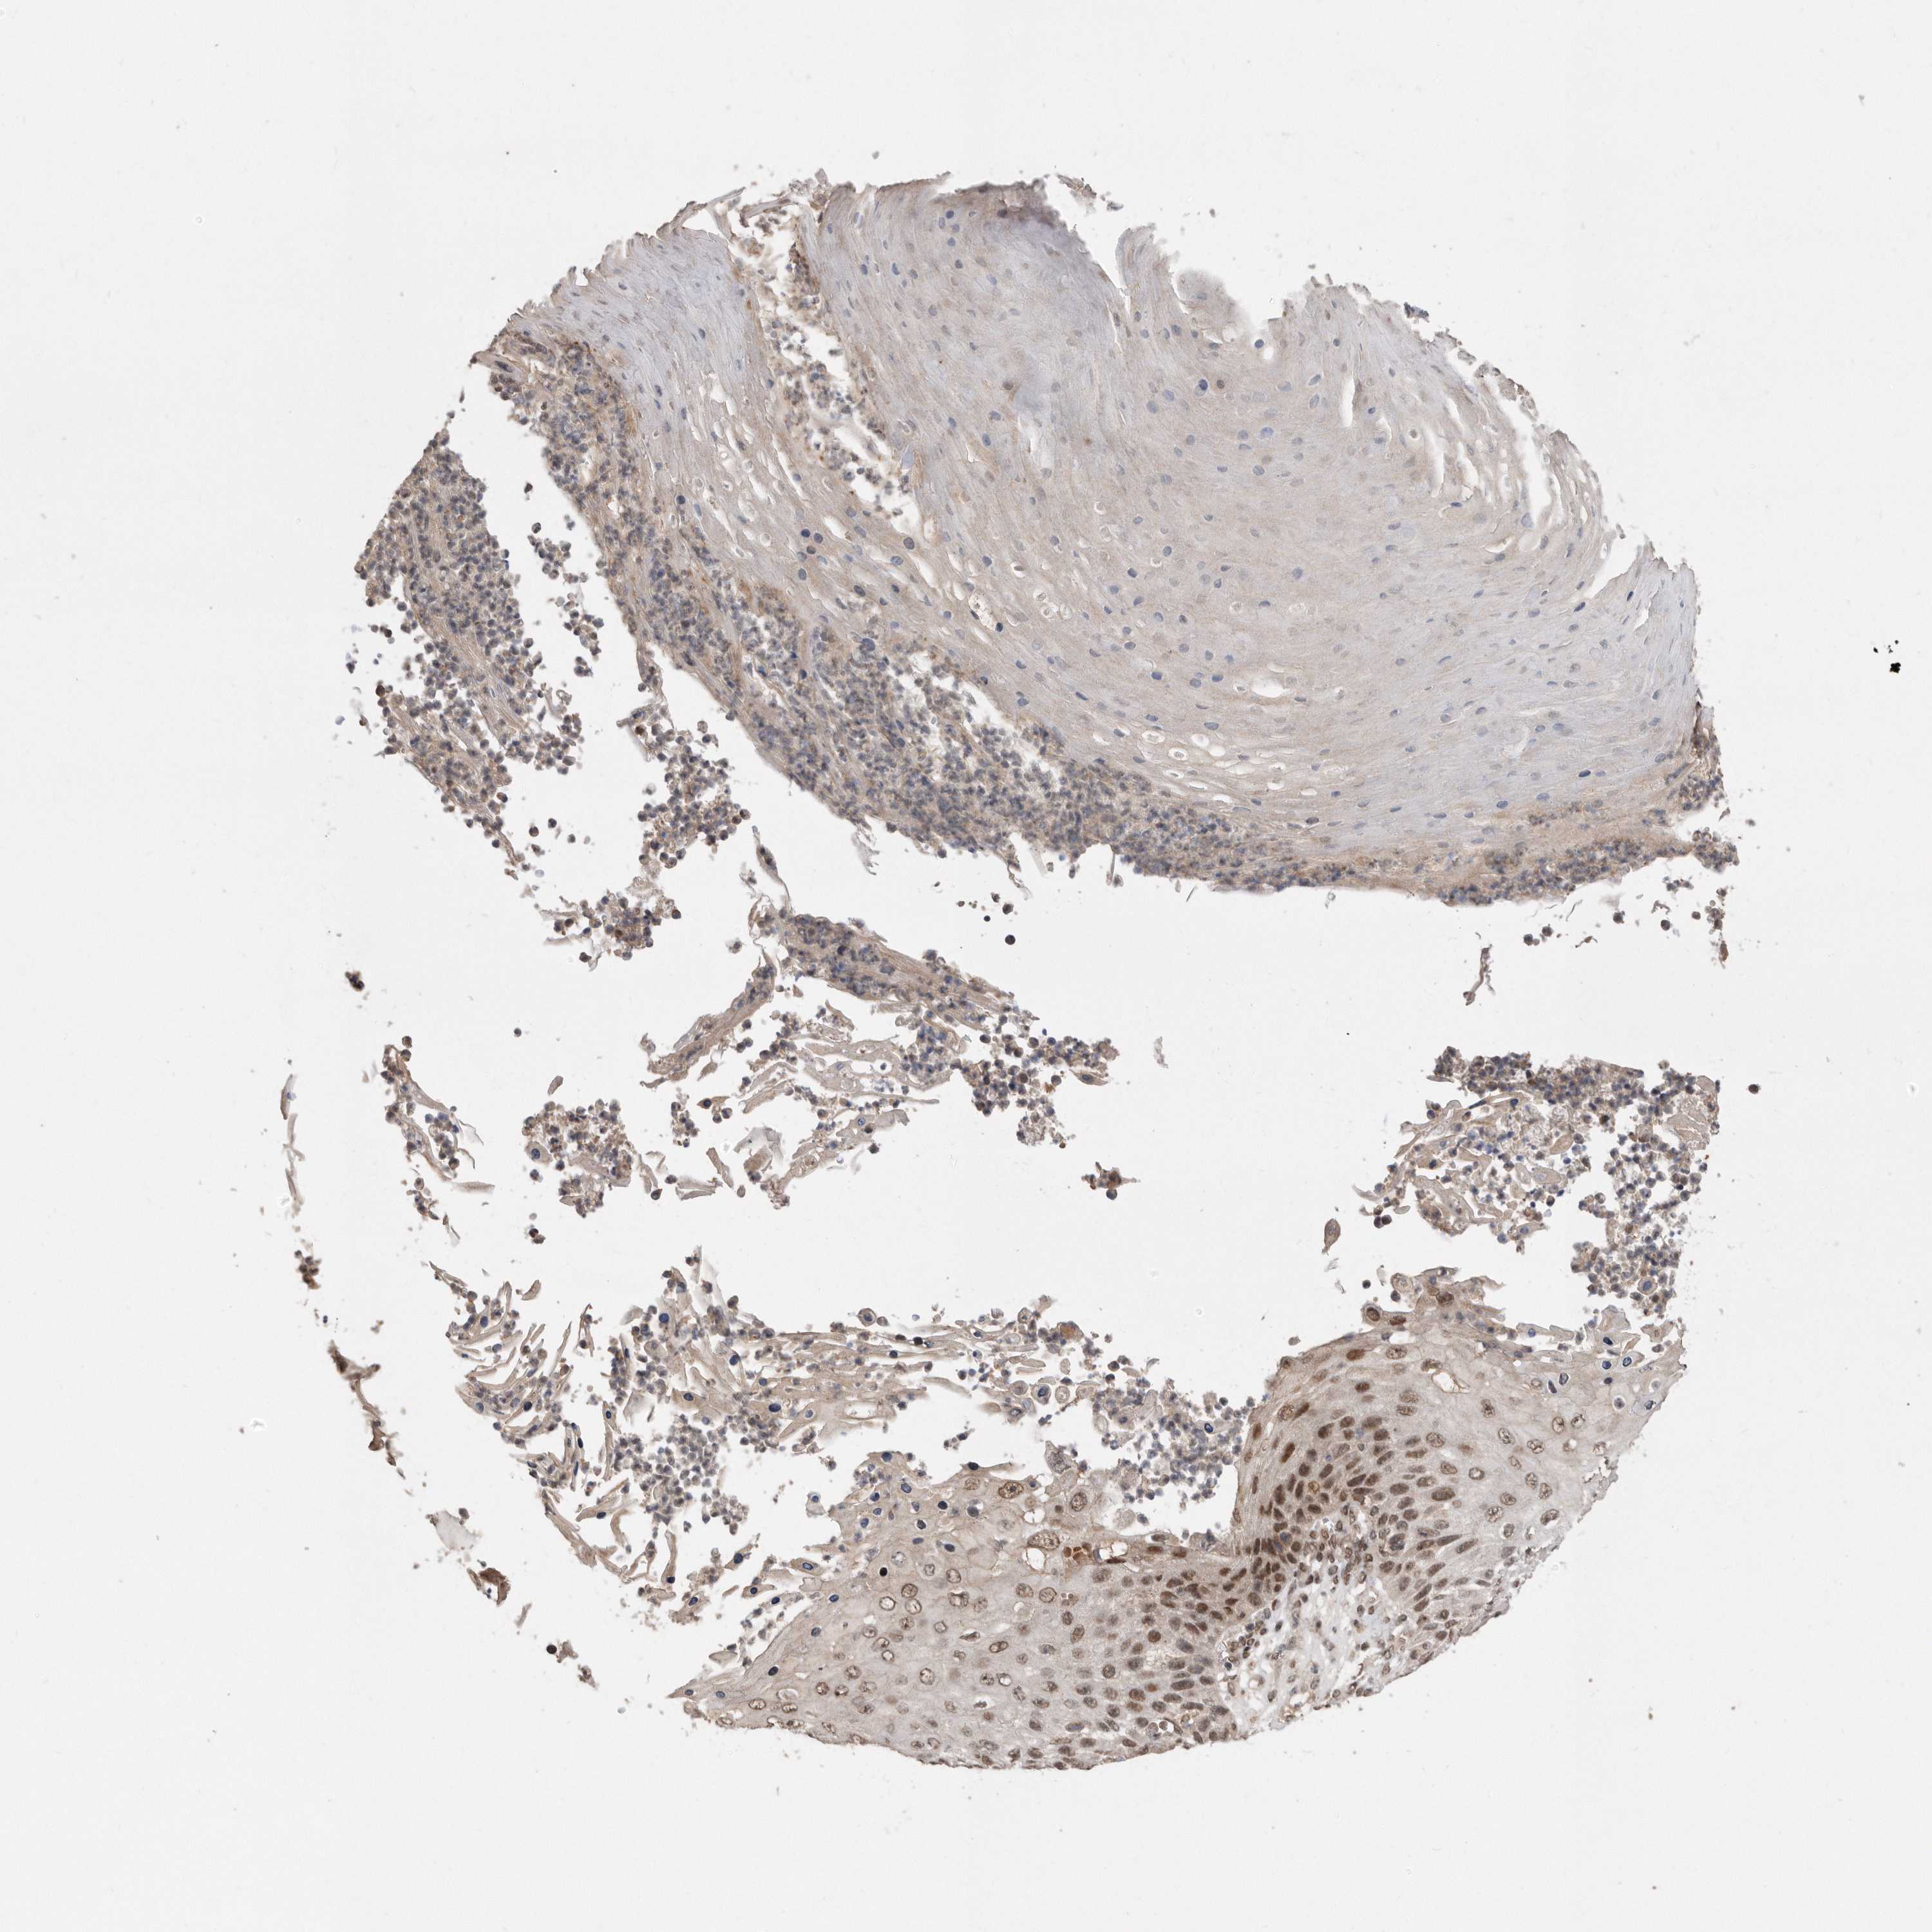

Basal cell and squamous cell cancer

SKIN CANCER - Protein expressioni

A mouse-over function shows sample information and annotation data. Click on an image to view it in a full screen mode. Samples can be filtered based on level of antibody staining by selecting one or several of the following categories: high, medium, low and not detected. The assay and annotation is described here.

Antibody stainingi

Antibody staining in the annotated cell types in the current human tissue is reported as not detected, low, medium, or high, based on conventional immunohistochemistry profiling in selected tissues. This score is based on the combination of the staining intensity and fraction of stained cells.

Each image is clickable and will lead to virtual microscopy that enables deeper exploration of all samples and also displays staining intensity scores, fraction scores and subcellular localization as well as patient and tissue information for each sample.

Antibody CAB034925

Staining

High

Intensity

Strong

Quantity

>75%

Location

Nuclear

Squamous cell carcinoma, metastatic, NOS